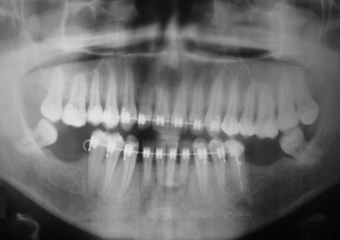

Raio X inicial